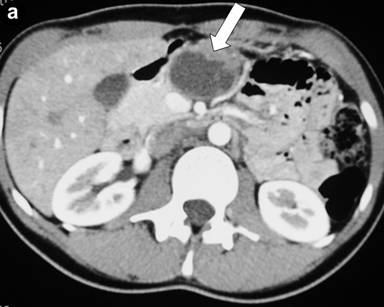

Postoperative histological examination of the resected specimen or taken biopsies revealed pancreatic metastases of extrapancreatic malignomas (Figure 1) in 8 patients (renal cell carcinoma, n=3; melanoma, n=2; duodenal gastrinoma, n=1; breast cancer, n=1; retroperitoneal liposarcoma, n=1). In 10 patients (52.6%) the following rare benign tumors were detected: solid pseudopapillary tumor of the pancreas (n=3) (Figure 2), mature teratoma of the pancreas (n=2) (Figure 3), capillary hemangioma of the pancreas (n=1) (Figure 4), intrapancreatic accessory spleen (n=1) (Figure 5), lymphoepithelial cyst of the pancreas (n=1) (Figure 6), hamartoma of the pancreas (n=1) (Figure 7), and pancreatic sarcoidosis (n=1). In one patient an advanced yolk sac tumor of the pancreas with peritoneal carcinosis was diagnosed (Table 2).

Figure 2. Solid pseudopapillary tumors of the pancreas (arrow). a. Preoperative CT scan. b. Intraoperative photograph. c. Histology of a solid pseudopapillary tumor of the pancreas with characteristic pseudopapillary morphology of monomorphous discohesive tumor cells on the left (arrow) and intratumoral foamy macrophages surrounding cholesterol clefts on the lower right (H&E-staining). |

In three patients (a 20-year-old female, a 51-year-old female, and a 26-year-old male) a solid pseudopapillary tumor of the pancreas was diagnosed. Solid pseudopapillary tumor (Franz tumor) accounts for less than 1% of all pancreatic tumors [32]. It is of low-grade malignancy but can cause extensive local invasion [33]. Our patients did not show any symptom which is typical for solid pseudopapillary tumors, that are commonly detected incidentally on imaging studies for other reasons [34, 35]. In the male patient a diagnostic biopsy of the tumor, that was carried out before referral to our department, revealed the diagnosis before surgery. The 20-year-old female had a family history of pancreatic cancer (uncle, grandmother). CT and MRCP in all patients showed solid and cystic fractions of the tumor. Butte et al. [36] published data of 45 patients with solid pseudopapillary tumors. Their results demonstrated that solid pseudopapillary tumors primarily occur in young women. Only about 8.3% of all cases were reported in males [37, 38]. About 15% are known to present with metastasis or recurrence [39]. The only feature associated with malignant disease is tumor size (7.8 vs.4.2 cm) at presentation [36]. In our patients tumors had a size between 2 and 4.5 cm and were located at different sites of the organ (head, body, tail). Oncologic outcomes in patients who undergo surgical resection are excellent [32]. This is in line with our observations. Until July 2011, 10 to 29 months after operation (Whipple operation, distal pancreatectomy, local excision of the solid pseudopapillary tumor), all patients are in good health without relapse. Surgery including enucleation is typically curative in patients with localized disease and possibly in patients with limited metastasis [40, 41, 42]. No consensus exists on an effective systemic therapy or radiation [43].